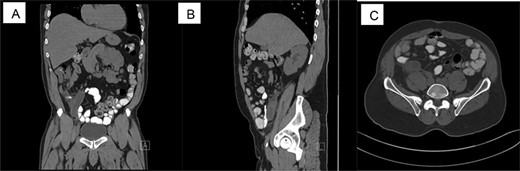

Pathology slides are: (A) low power view: appendix with thicken wall, (B) high power view: signet ring cell, (C) synaptophysin stain: positive and (D) chromogranin stain: focally positive.

During surgery, the appendix was noted to be adhered to the abdominal wall and multiple adhesions to the surround mesentery at the base of the appendix. The appendix measured 10.5 cm in length × 1–2 cm in diameter when it was extracted and sent to pathology (Fig. 1). The serosa of the appendix was dull and hemorrhagic. There was a firm area measuring 2.5 cm at the base. On pathology, the cuts revealed a gray white homogeneous appearing tumor measuring 2.5 × 0.7 × 1.3 cm located at the proximal appendix with positive lymphovascular invasion (T3, NX, MX). Pathology results showed carcinoma of ex-goblet cell carcinoid, signet ring cell type (Fig. 2). Microscopic findings indicated the involvement of muscularis propria into subserosa of mesoappendix with the absence of tumor perforation. Immunohistochemical staining revealed positive staining for chromogranin and synaptophysin, supporting the diagnosis (Fig. 2).

The mean average age for this specific type of appendiceal carcinoma is 62 years old and has a propensity for those who are Caucasain, with a male to female ratio of 1:11. To further support a diagnosis, the immunohistochemical staining is of vital importance; in our case, it was chromogranin and synaptophysin positive. Another important stain that is specific for signet ring cell carcinoma is CDX-2, caudal-type homeobox transcription factor 2, marker, but that was not available for this case [1, 6].